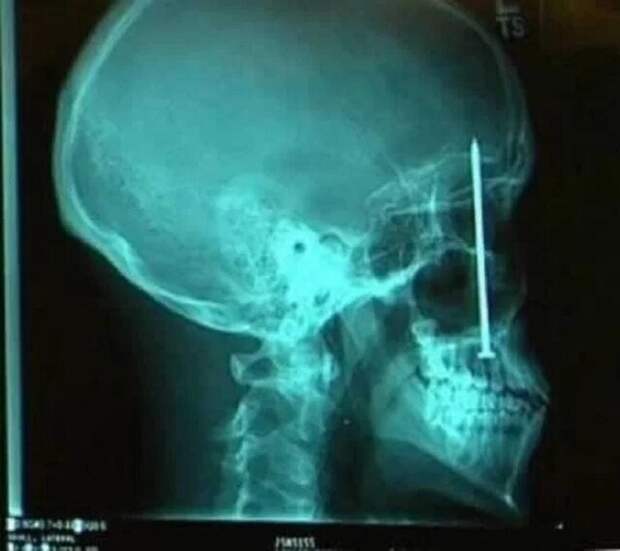

Сканирование аорты, самой большой артерии нашего тела  Травма головы

Травма головы  Кровеносные сосуды в пальце